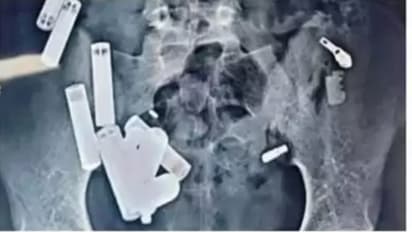

आगरा। उत्तर प्रदेश के हाथरस से 14 वर्षीय आदित्य शर्मा की दर्दनाक मौत ने सबको झकझोर दिया है। दिल्ली के सफदरजंग अस्पताल में डॉक्टरों ने आदित्य के पेट से पांच घंटे की जटिल सर्जरी में 65 वस्तुएं निकालीं, जिनमें बैटरी, चेन, रेजर, ब्लेड के टुकड़े और स्क्रू शामिल थे। हालांकि, सर्जरी के बाद भी डॉक्टर उसे बचा नहीं पाए, और उसकी मौत संक्रमण के कारण हुई।

नोएडा में डॉक्टरों ने जांच के दौरान उसके पेट में 42 वस्तुएं और पाईं, जिससे तुरंत उसे दिल्ली के सफदरजंग अस्पताल ले जाया गया। वहां डॉक्टरों ने स्कैन में "कुल 65 वस्तुएं" पाईं और इस स्थिति में उसकी हृदय गति 280 प्रति मिनट तक पहुंच गई थी। पांच घंटे की सर्जरी के बाद भी डॉक्टर उसे नहीं बचा सके और उसकी दर्दनाक मौत हो गई।